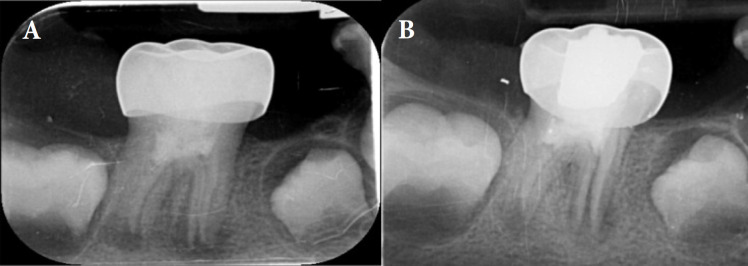

In this case report, the regeneration method was used to treat the previously treated first molar, which presented with symptoms of pain during chewing and secondary acute apical periodontitis. Due to the importance of preserving the patient's permanent teeth in order to maintain optimal space and function, the regeneration treatment was performed in two visits and according to the American Association of Endodontists (AAE) guidelines. The continuation of tooth root development, healing of periapical radiolucency and positive response to sensibility test (cold test) were observed during follow-up radiographs at intervals of 6 months, 1 year & 2 year.